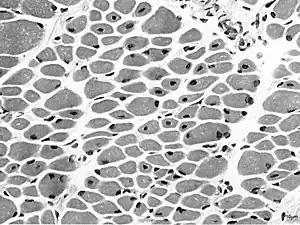

Muscle biopsy from the quadriceps taken at 3 months of age from a girl with X-linked centronuclear ("myotubular") myopathy due to a mutation in the myotubularin (MTM1) gene and extremely skewed X-inactivation (H&E stain, transverse section). Note marked variability in fibre size, moderate increase in connective tissue and numerous central nuclei.

On examination of muscle biopsy material, the nuclear material is located predominantly in the center of the muscle cells, and is described as having any "myotubular" or "centronuclear" appearance. In terms of describing the muscle biopsy itself, "myotubular" or "centronuclear” are almost synonymous, and both terms point to the similar cellular-appearance among MTM and CNM. Thus, pathologists and treating physicians use those terms almost interchangeably, although researchers and clinicians are increasingly distinguishing between those phrases.

In general, a clinical myopathy and a muscle biopsy showing a centronuclear (nucleus in the center of the muscle cell) appearance would indicate a centronuclear myopathy (CNM). The most commonly diagnosed CNM is myotubular myopathy (MTM). However, muscle biopsy analysis alone cannot reliably distinguish myotubular myopathy from other forms of centronuclear myopathies, and thus genetic testing is required.Diagnostic workup is often coordinated by a treating neurologist. In the United States, care is often coordinated through clinics affiliated with the Muscular Dystrophy Association.